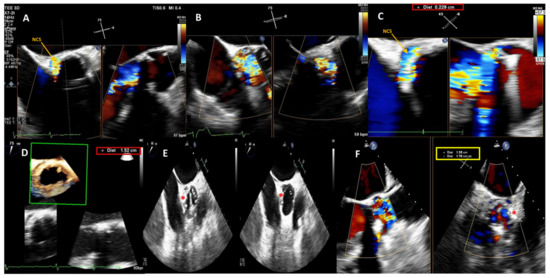

Technical Recommendations for Real-Time Echocardiography and Fluoroscopy Imaging Fusion in Catheter-Based Mitral Valve Paravalvular Leak and Other Procedures

Widespread catheter-based interventions for structural heart disease have overtaken the treatment of paravalvular leaks (PVL). Multimodality imaging techniques play a crucial role in accurate diagnosis, procedure planning and performance. However, PVL closure is often technically challenging due to the complex anatomy of the [...] Read more.

Widespread catheter-based interventions for structural heart disease have overtaken the treatment of paravalvular leaks (PVL). Multimodality imaging techniques play a crucial role in accurate diagnosis, procedure planning and performance. However, PVL closure is often technically challenging due to the complex anatomy of the defects and their relation to surrounding anatomical structures. The application of echocardiography and fluoroscopy imaging fusion (EFF) may simplify challenging imaginative three-dimensional reconstruction of the intracardiac anatomy and facilitate the procedure. To master new technology, personnel must make cognitive changes, overcome a learning curve, and obtain adequate theoretical knowledge. Main aim of this manuscript is to present basic recommendations for EFF application in practice, alongside, each scenario is supported by technically challenging clinical examples. We may conclude that our manuscript may provide useful information for physicians on EEF application in clinical practice. Full article

Show Figures

Figure 1